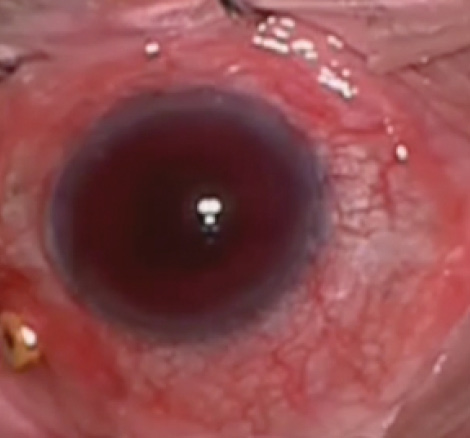

Figure 2. Anterior chamber hemorrhage prior to the first washout procedure.

Figure 3. Ultrasound biomicroscopy of the iris-sutured IOL shows significant contact with the iris, causing trauma with pigment dispersion and recurrent hemorrhage.

I diagnosed uveitis-glaucoma-hyphema (UGH) syndrome, likely caused by the iris-sutured IOL’s rubbing on the posterior iris surface (Figures 2 and 3). Another washout was performed as well as an IOL exchange. To move the IOL away from the iris, I replaced the iris-sutured IOL with a sclera-sutured lens. The patient’s UCVA improved to 20/50, but 2 weeks later, the hyphema and vitreous hemorrhage returned. The IOP began to rise into the high 20s despite maximum topical glaucoma medications.